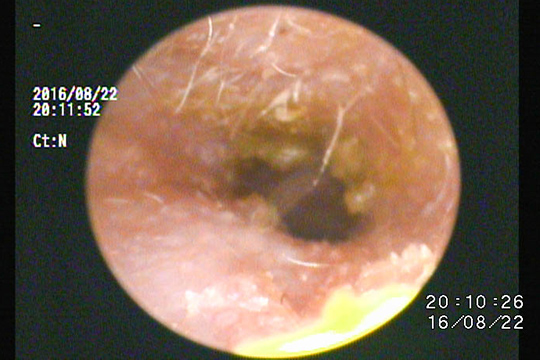

硬い耳垢です。

このタイプは通常の耳掃除では綺麗になりません。

耳垢を溶解するクリーナーを使用します。

除去困難な場合は内視鏡を使用して取り除きます。

ベトベトした耳垢です。

このような場合、耐性菌などの感染症が起こっている場合と、鼓膜が破れて中耳炎になっている場合が考えられます。

鼓膜の確認と細菌培養、場合により鼓室内洗浄などを行います。